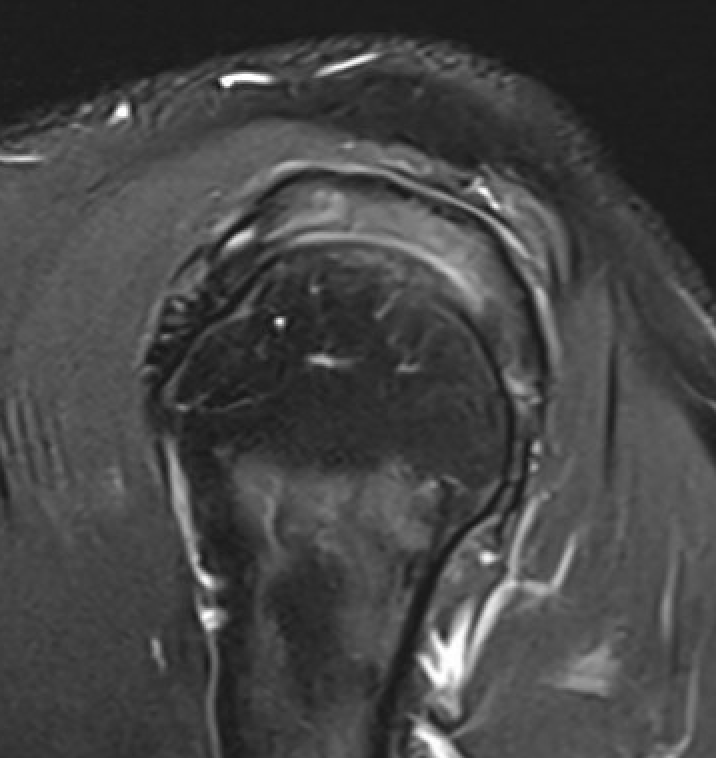

MRI

Inflammation and thickening of the rotator cuff tendons

Mild inflammation of the supraspinatus tendon insertion

Thickening and edema of the supraspinatus and infraspinatus tendon

Subscapularis tendinosis